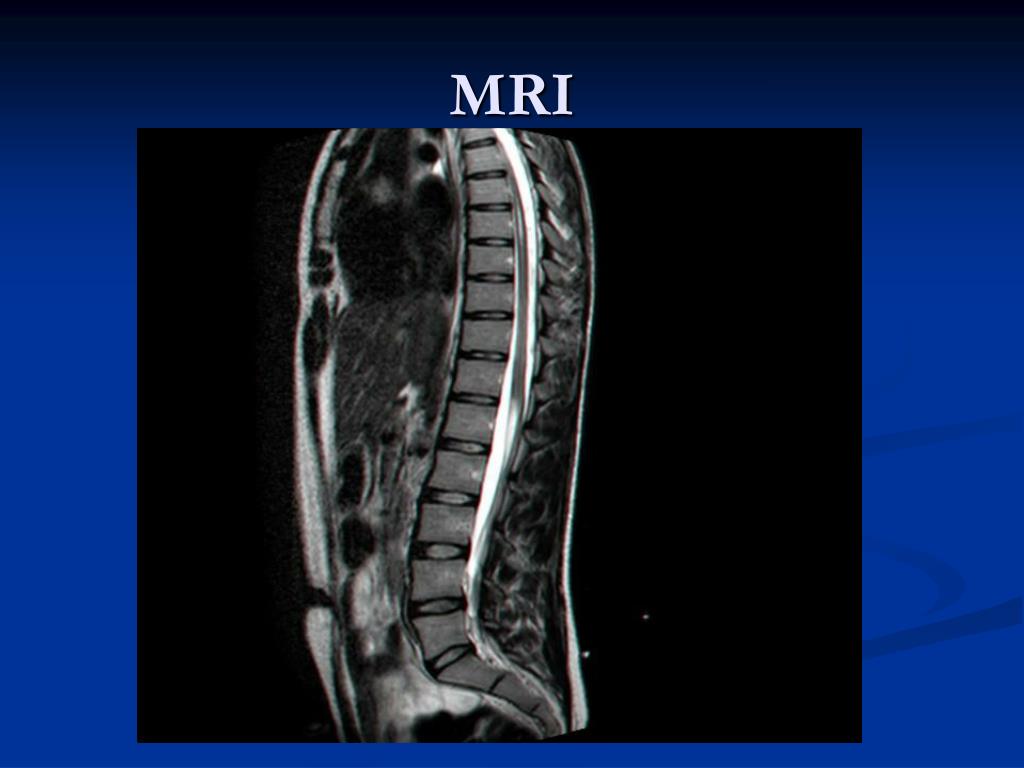

4. MRI

5. MRI

6. MRI

15. WNV MYELITIS = WNV POLIOMYELITIS-LIKE SYNDROME Acute and asymmetric flaccid paralysis occurs in about 10% of the patients who are hospitalized for WNV infection. Neurological lesion is localize in the anterior horn motor neurons. CSF-moderate pleocytosis of few hundred lymphocytes, protein is moderately elevated , glucose is normal. MRI of the spinal cord – high signal intensity on T2-weighted scans in anterior horns .